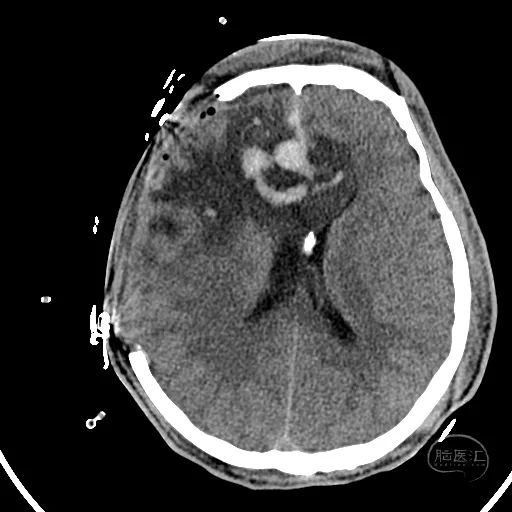

术后第一天复查CT显示后颅窝血肿清除,第四脑室隐约可见。

患者昏迷状,GCS评分3分,双侧瞳孔等大等圆,直径3mm,对光反射迟钝。

额叶血肿清除后,水肿明显。

额叶残余少量血肿,脑室引流管在位。

骨窗见枕骨大孔开放。术中清理枕骨大孔骨折时,无明显出血。